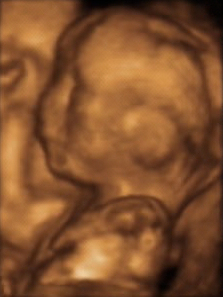

3D超声图像:20周胎儿的三维表面渲染图像,可清晰显示胎儿面部轮廓